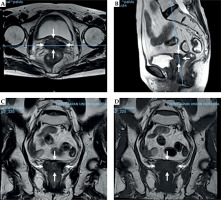

Fig. 4

Pre-treatment magnetic resonance images of patient No. 1. A) T2 fast spin echo (FSE) transverse section, B) T2 FSE sagittal section, C) T2 FSE coronal section, and D) T1 FSE coronal section. White arrow represents the margin of vaginal stump tumors

A 65-year-old woman had undergone hysterectomy due to adenomyosis, which was characterized by the presence of endometrial tissue within the muscular walls of the uterus. However, six years later, she was admitted to the hospital due to experiencing irregular vaginal bleeding. After MR examination, a tumor measuring 5.2 cm × 3.0 cm × 5.2 cm was discovered in the vaginal cuff in the upper third of the vagina (as shown in Figure 2). Pathological examination revealed squamous cell carcinoma. The patient was scheduled to receive whole pelvis EBRT, with the dose of 45 Gy in 25 fractions, weekly concomitant cisplatin (40 mg/m2), combined with MR image-guided BT (MR-IGBT) of 28 Gy in four fractions, two fractions within one application with at least 12 hours interval between two fractions, and at least one week interval between two applications.

Pre-treatment magnetic resonance images of patient No. 2. A) T2 fast spin echo (FSE) transverse section, B) T2 FSE sagittal section, C) T2 FSE coronal section, and D) T1 FSE coronal section. White arrow represents the margin of vaginal stump tumors